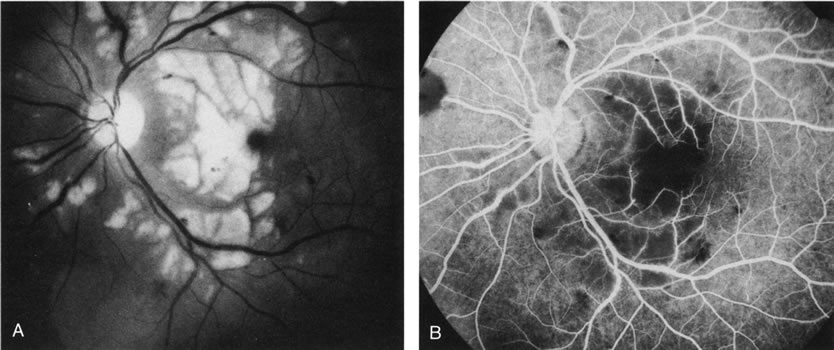

Trauma can induce a wide spectrum of alterations of the retina, RPE, and choroid. Most types of traumatic maculopathy, such as Purtscher's retinopathy, Berlin's edema, retinal contusion, traumatic macular hole, and choroidal rupture, are readily apparent on clinical examination.257 Choroidal rupture, althoughe usually evident clinically, may be more obvious on FA (Fig. 39). Contusion necrosis of the RPE may present clinically with an associated RPE detachment, an overlying neurosensory detachment, and a subtle change in RPE pigmentation. FA can demonstrate the site of leakage into the subretinal space, unless the RPE defect has healed by the time of testing. FA is particularly helpful in differentiating retinal concussion (Berlin's edema), in which FA findings are normal, from retinal contusion, in which there is RPE damage and, consequently, increased transmission of choroidal fluorescence on FA.257 In Purtscher's retinopathy, FA can document vascular closure, which accounts for the retinal infarctions (Fig. 40).258

Fig. 40. Purtscher's retinopathy. A. Red-free photograph demonstrates retinal whitening owing to ischemia/infarction. This patient had sustained a severe blunt chest injury in an automobile accident. B. Fluorescein angiogram demonstrates nonperfusion of the retinal capillaries, particularly in the perifoveal area. (Courtesy of Dr. Kenneth G. Noble.)